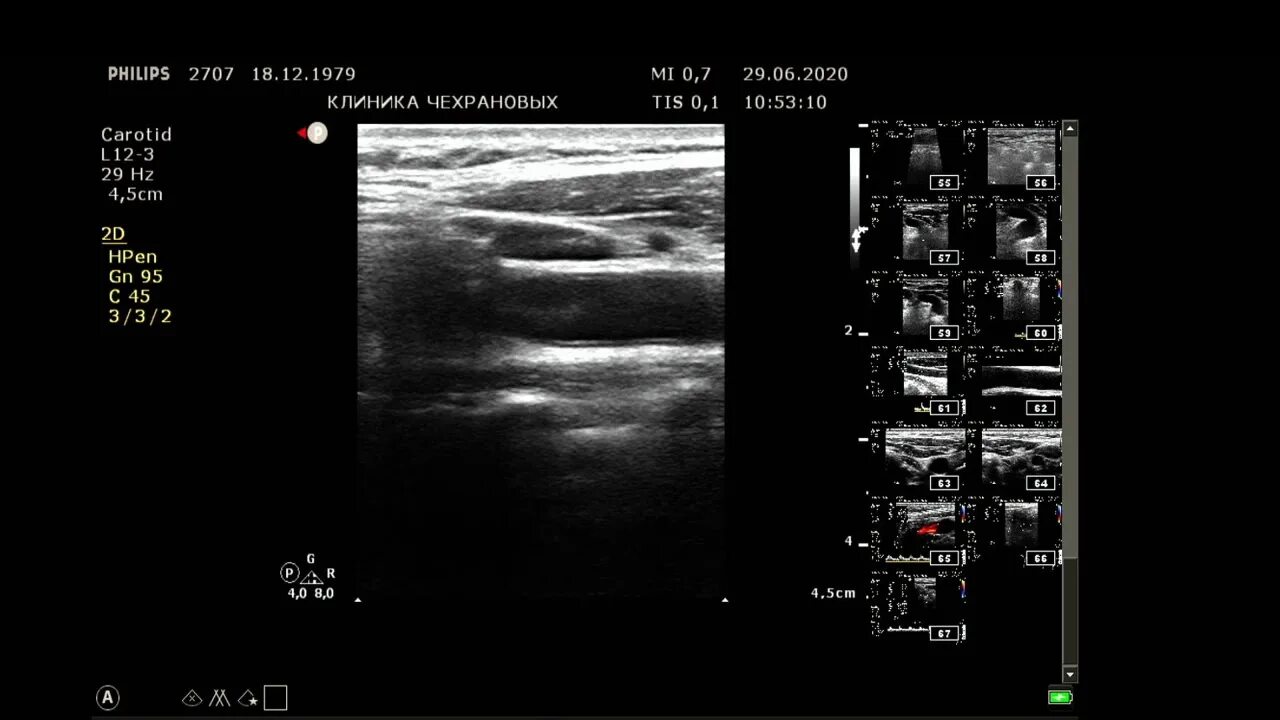

Сделать узи сонной артерии